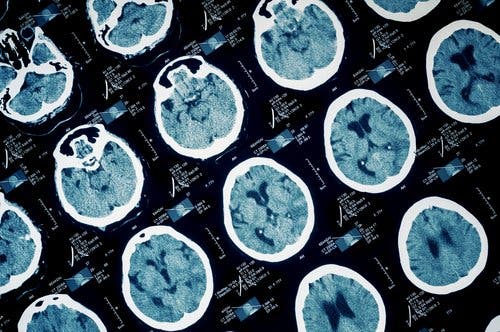

- Esclerosis Múltiple.

- Síntomas neurológicos.